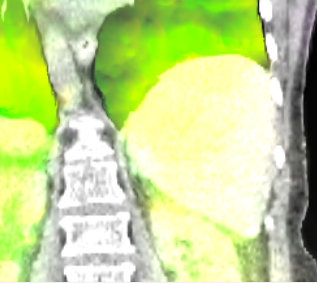

Figure 4: Coronal views with overlayed motion field to the CT data of the patient pat3D𝑝𝑎𝑡3𝐷pat3D (a-d) deformed with the model of pat4D𝑝𝑎𝑡4𝐷pat4D. The color wheel legend below indicates the direction of the motion field.

(a) First time point.

Refer to caption

(b) Second time point.

(c) Third time point.

(d) Fourth time point.

(e)